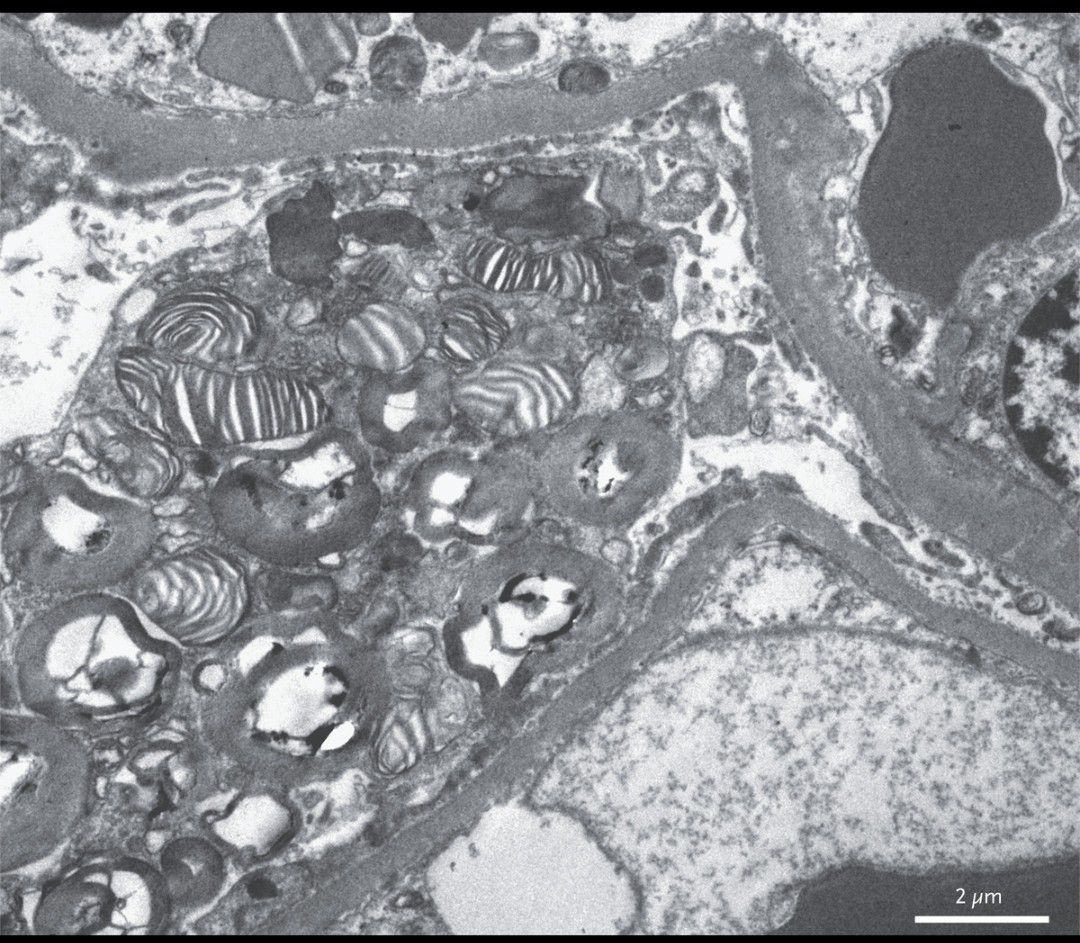

A 21-year-old man with a 10-year history of intermittent burning pain in his arms and legs presented to the nephrology clinic after noticing foamy urine for 1 month. The physical examination, which included a neurologic evaluation, was unremarkable, but urinalysis revealed proteinuria. The serum creatinine level was 81 μmol per liter (0.9 mg per deciliter) (reference range, 62 to 106 μmol per liter [0.7 to 1.2 mg per deciliter]), and the urinary protein excretion was 1335 mg per 24 hours (reference range, 0 to 140). Biopsy of the kidney showed the presence of vacuoles within podocytes. Electron microscopy revealed layered membrane structures appearing as so-called zebra bodies within enlarged lysosomes in the podocytes. A diagnosis of Fabry’s disease was confirmed when a mutation in the gene encoding alpha-galactosidase A (GLA) was detected. Fabry’s disease is an X-linked lysosomal storage disorder caused by mutations that result in low or absent activity of the enzyme alpha-galactosidase A. This deficiency results in the accumulation of globotriaosylceramide in cells, resulting in the formation of the characteristic zebra bodies. Treatment of Fabry’s disease includes enzyme-replacement therapy; however, this treatment was not available where the patient was living. Carbamazepine was initiated for pain management. At the 10-month follow-up, he continued to have proteinuria but had a normal creatinine level, and his pain was well controlled.